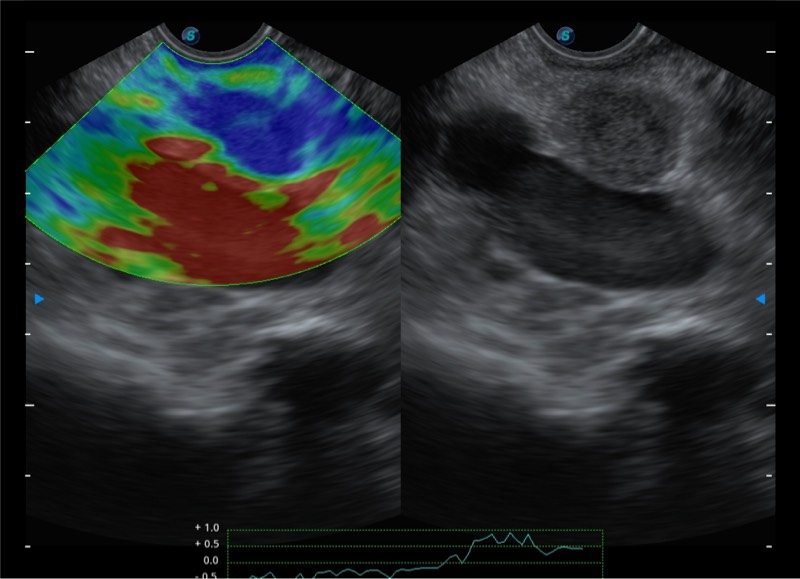

基于二十年的超声技术积累,milan米兰提供了最新一代的独立超声主机,在提供高质量图像的同时满足多学科使用。具备常见多普勒技术并提供弹性成像、声学造影等高端影像技术。新一代传感器具有更强的抗干扰能力并减少图像伪影。

4-12MHZ宽频输出